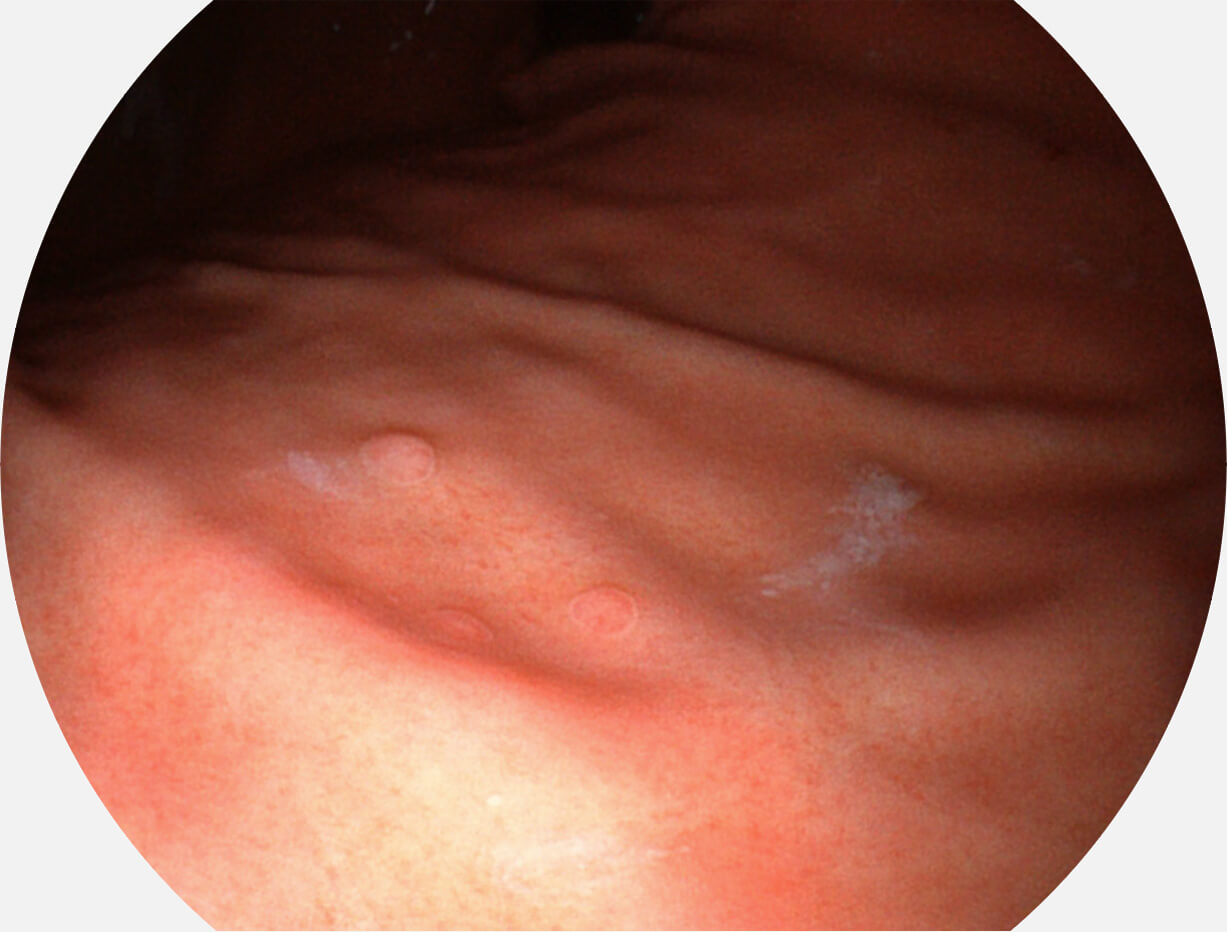

强调浅层黏膜结构的同时,保证照明亮度和提升浅层微血管与中层血管颜色对比度,病变边界更清晰。

白光图像